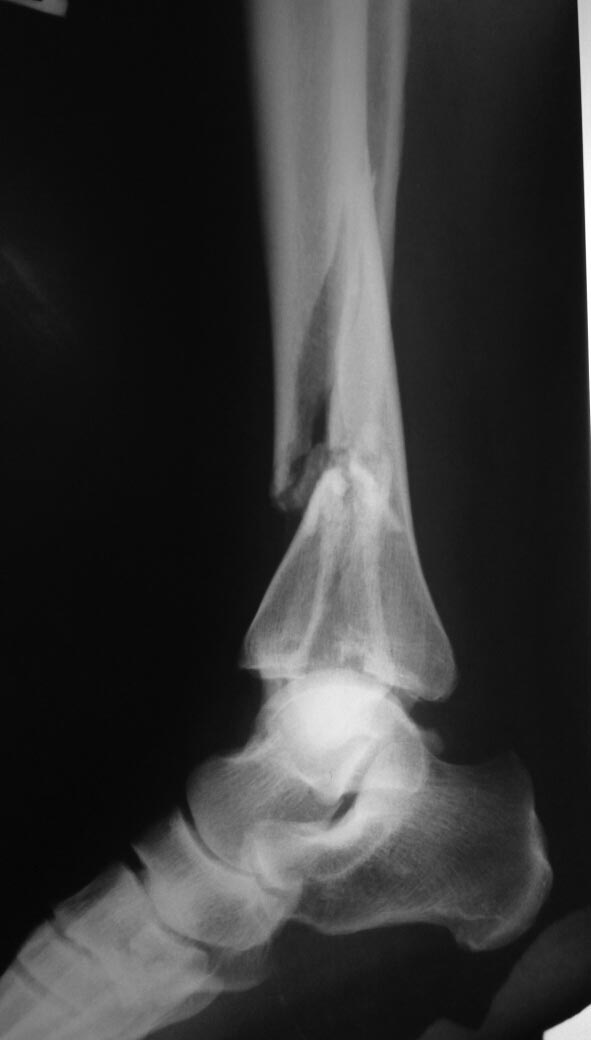

Re: перелом типа "Пилон".

добавляю прямой. КТ к сожалению нет.